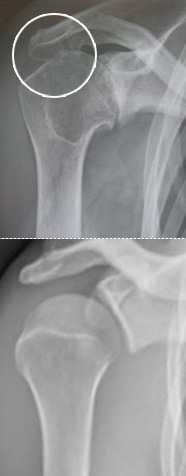

Abb 2; Röntgen ener Arthrose des Schultergelenks (oben) im Vergleich zu einer gesunden Schulter

Abb 3; Röntgen eines Impingementsyndroms der Schulter (oben) im Vergleich zu einer gesunden Schulter

Seit seiner Erfindung Ende des vorigen Jahrhunderts, ist das Röntgen eine gute und wertvolle Untersuchungsmethode geblieben. Im Röntgen kann das knöcherne Skelett besser beurteilt werden als in vielen modernen Untersuchungsverfahren. Knochen kommt in den meisten Fällen weiß zur Darstellung, wohingegen Weichteilgewebe schwarz erscheint. Der Zustand des Knochens kann direkt beurteilt werden.

Da Arthrosen (= Gelenksabnützungen) ganz typische Veränderungen am Knochen hervorrufen, lassen sich diese am Besten und Schnellsten auf einem Röntgenbild diagnostizieren. Weichteilgewebe wie Muskeln, Sehnen, Knorpel, Meniskus, Bandscheiben etc. kann man dagegen im Röntgen nicht sehen. Man kann dennoch, wenn auch eingeschränkt, Rückschlüsse auf diese Strukturen ziehen. Wenn zum Beispiel kein Abstand mehr zwischen Schulterkopf und Gelenkspfanne sichtbar ist, so bedeutet das, dass der Knorpelbelag fehlt, was auf eine Arthrose (= Gelenksabnützung) schließen lässt (Abb 2).

Zur Beurteilung eines Schultergelenkes benötigt der Fachmann in der Regel zu den 2 Standardebenen „Schulter ap“ und „axial“ noch eine dritte Ebene; die „Y Aufnahme“. Auf dieser kommen Knochensporne wie z.B. beim Impingementsyndrom besser zur Darstellung (Abb 3).